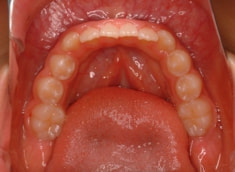

治療開始から約10ヶ月後

治療分析:日本人の反対咬合や下顎前突は、上顎の劣成長を伴なうことが多いので、上顎を側方拡大と前方に牽引しました。側方拡大方法は急速拡大で、正中口蓋縫合の拡大を行い、横口蓋縫合を剥がす効果で、前方牽引の効果を促進します。